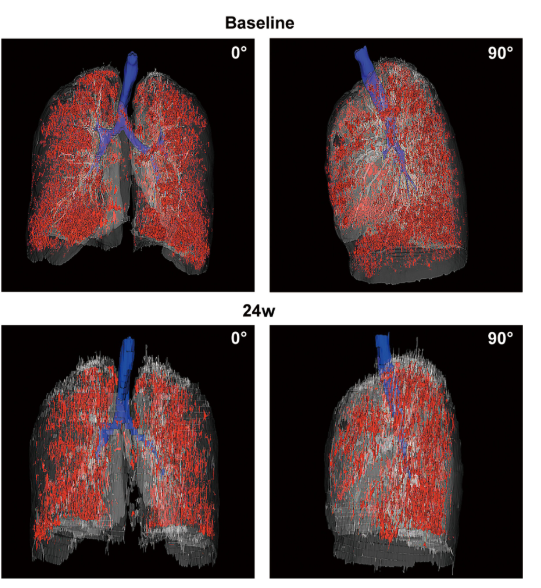

影像学检查:对于患者 #2902,定量分析显示基线时总体肺气肿面积比为 12.75%,移植后 24 周降至 10.02%。在患者 #8009 中,肺气肿面积比值从基线的 10.85% 下降到移植后 12 周的 9.08%。CT 图像的三维可视化显示,肺气肿的减轻在下叶比在上叶更明显。